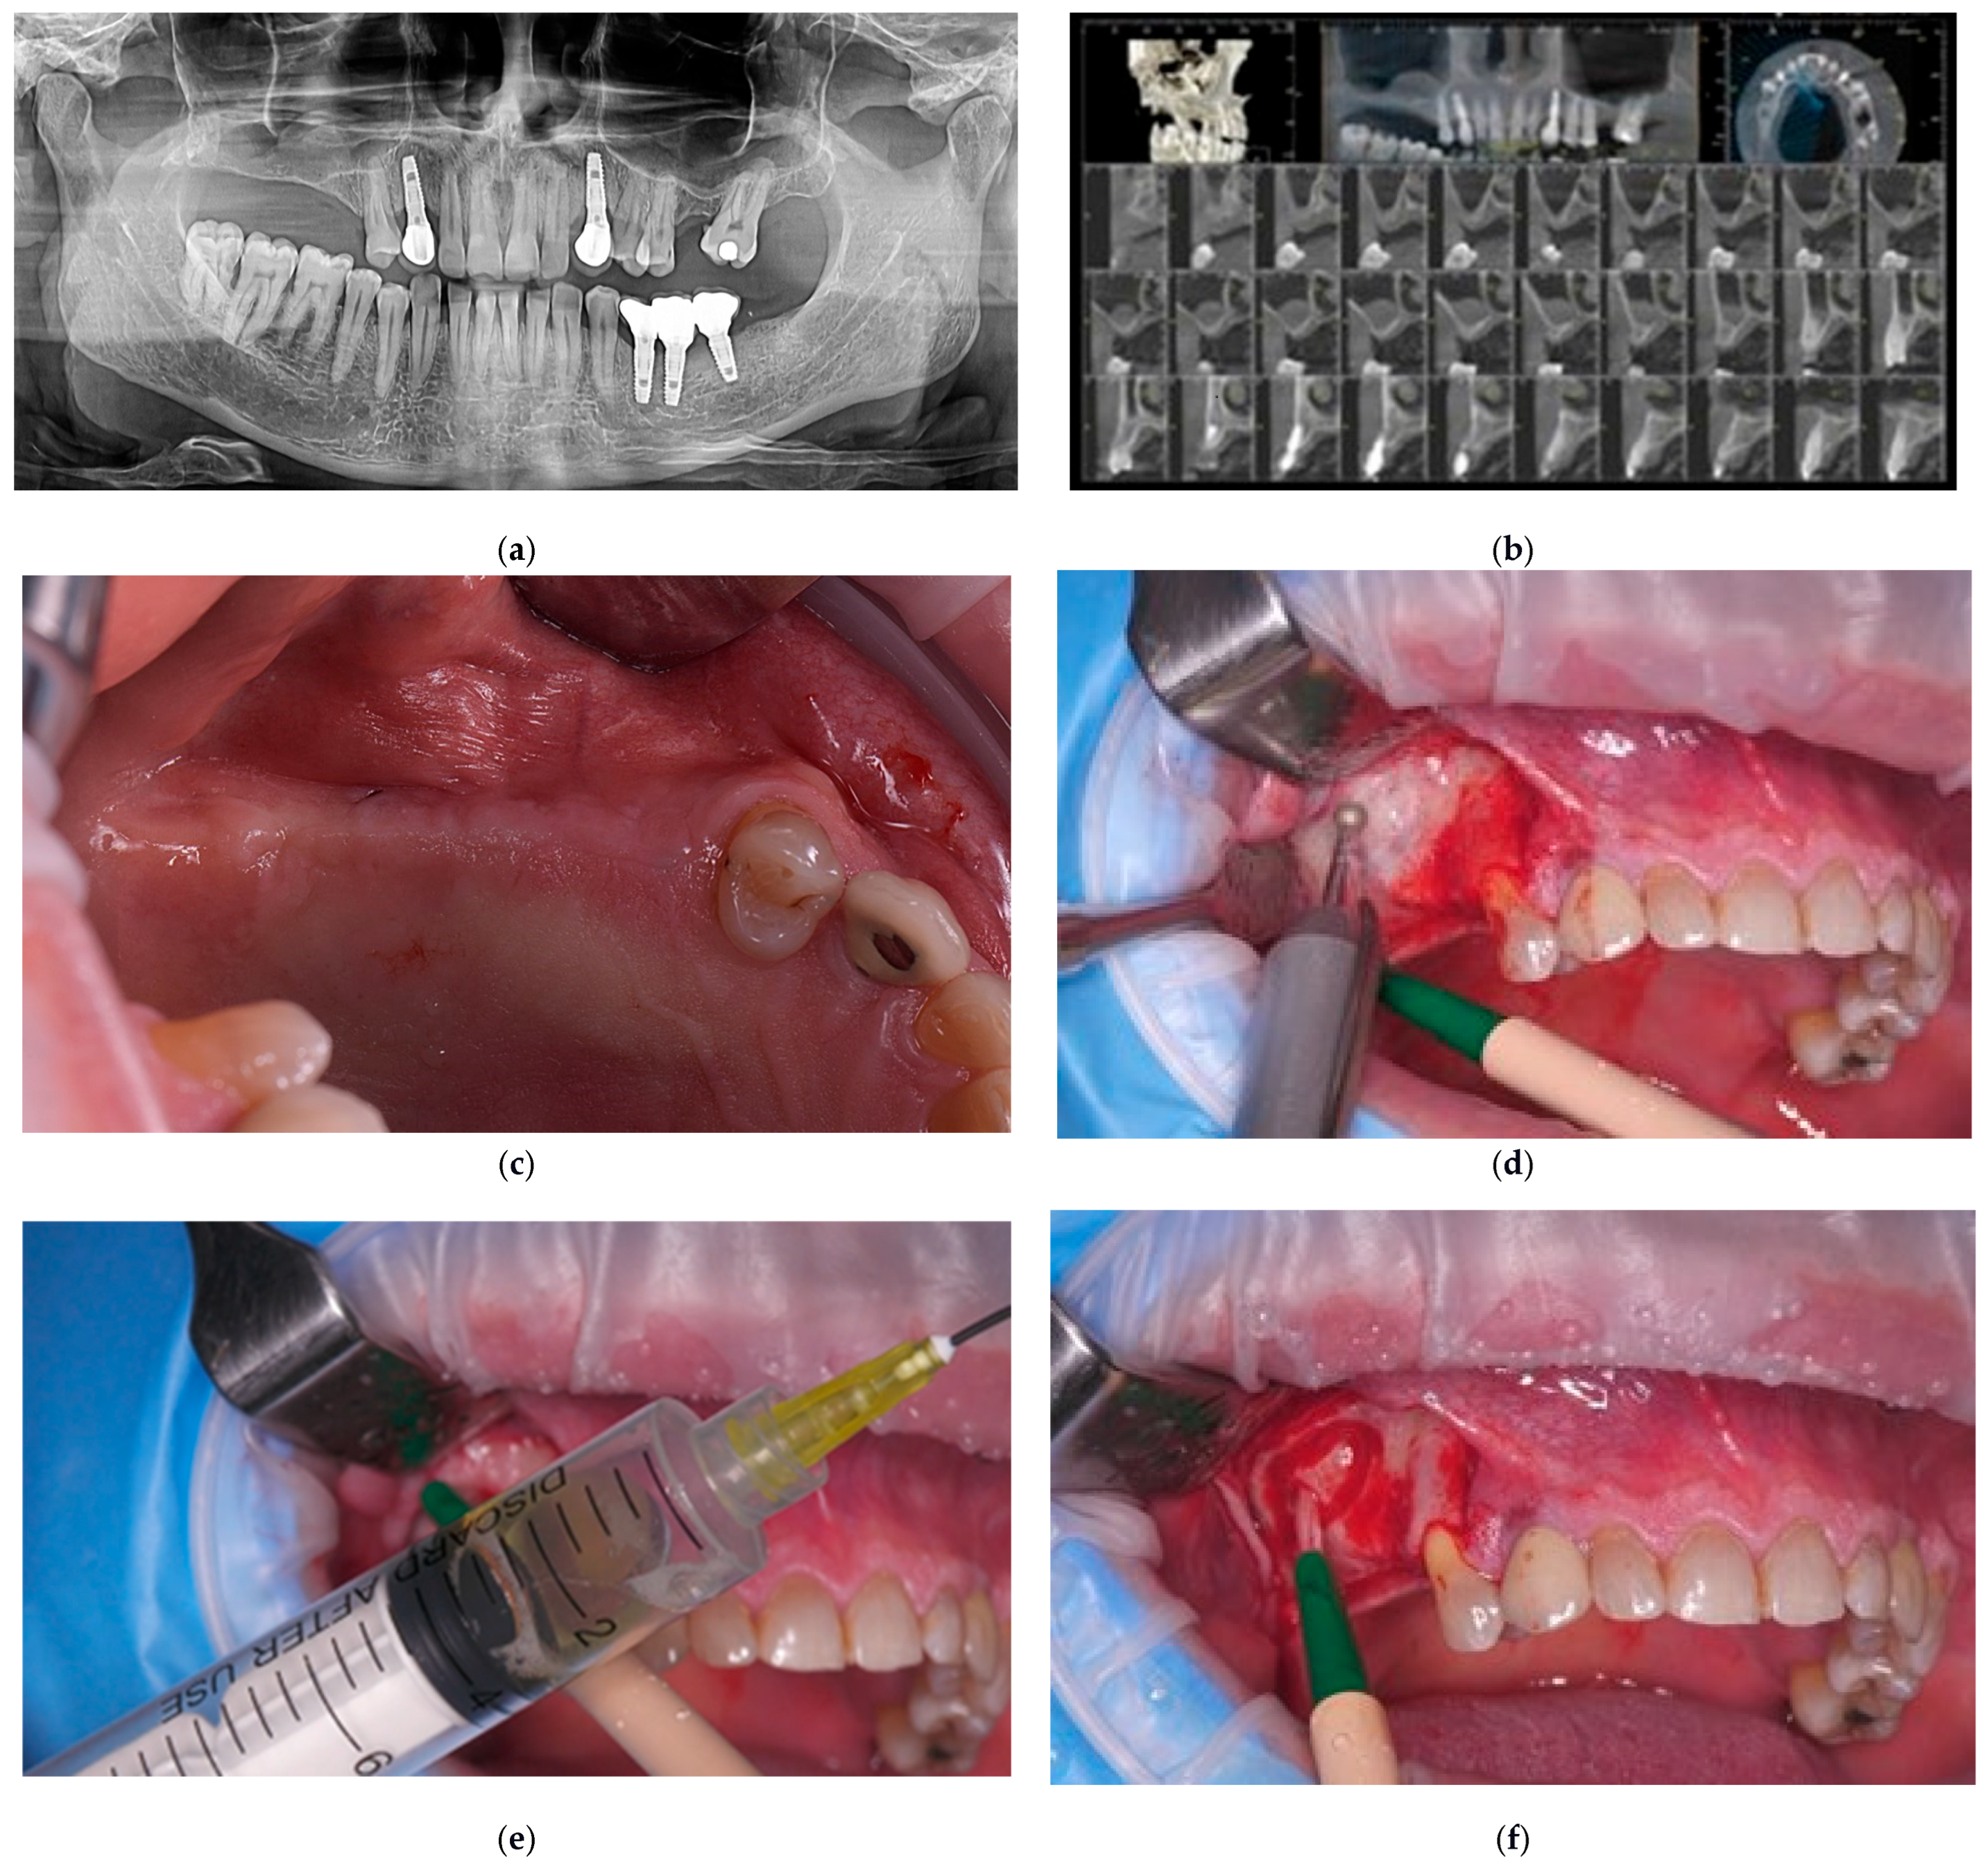

3.1. Clinical Outcomes

| 1. | F | 49 | 24 May 2021 | Lateral sinus lift with staged implantation | none | none | 4.7 | 2.5.; 2.6.; 2.7. | 2 | 15 | 13 | 52.23 |

| 2. | M | 56 | 9 August 2021 30 November 2021 |

| Intentional perforation for mucocele removal | none | 3.7 | 1.5.; 1.6.; 1.7. | 1 | 10 | 9 | 49.73 |

| 3. | M | 46 | 22 July 2021 | Lateral sinus lift with staged implantation | none | 7.5 | 2.6.; 2.7. | 1 | 15 | 14 | 38.3 | |

| Baseline (Month 0) | Pre-operative evaluation | Clinical exam; CBCT confirming severe posterior maxillary atrophy; treatment planning |

| Day 0 | Lateral sinus augmentation | Collagenated porcine xenograft (THE Graft™); lateral window approach; one case: controlled Schneiderian membrane perforation for mucocele removal and collagen membrane repair |

| Months 3–8 | Implant placement and biopsy | Core specimens collected during implant osteotomy; histology (H&E, Masson–Goldner) + TRAP staining |

| Months 12–52 | Follow-up period | Stable marginal bone levels (<1 mm first year); no complications; graft volume maintained |

| 46.8 months (mean) | Long-term evaluation | All implants functional; radiographic and clinical stability confirmed |

| 52.2 months (max) | Long-term | CBCT and periapical radiographs from available case demonstrating stable bone height and osseointegration |